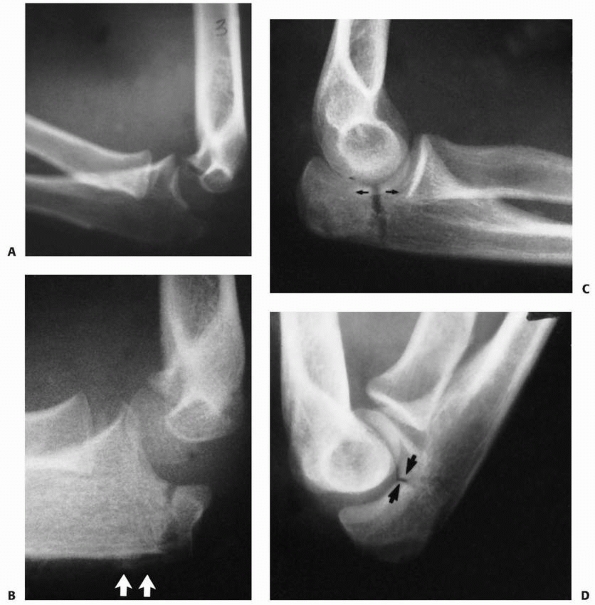

![]() |

FIGURE 11-4 A,B. AP and lateral radiographs demonstrating a radial neck fracture in a patient with a nonossified proximal radial epiphysis. C. Arthrogram prior to reduction demonstrating location/displacement of nonossified proximal radial epiphysis. D-F.

Arthrogram/radiographs after reduction with intramedullary technique. (From Javed A, Guichet J.M. Arthrography for reduction of a fracture of the radial neck in a child with a nonossified radial epiphysis. J Bone Joint Surg Br 2001;83-B:542-543, with permission.) |